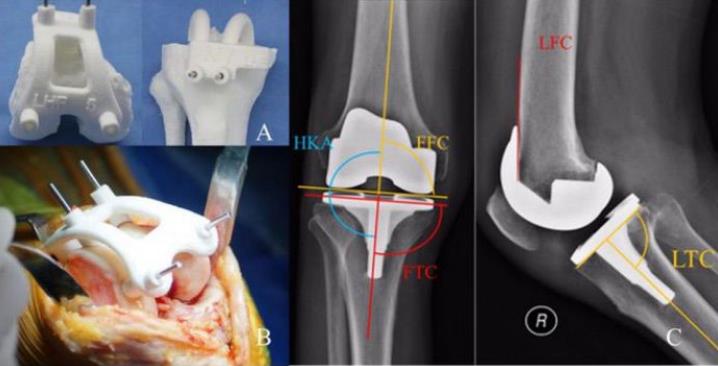

家屬了解情況后,立即給阿婆辦理了住院手續。骨一科主任李松軍在得知情況后,立即讓管床醫生快速完善了術前檢查,并利用下肢CT數據進行建模,3D打印個性化手術導板。檢查結果出來后,發現阿婆心功能極差,心臟射血分數只有40%(正常值為50%-70%),且有房顫伴預激綜合征、高血壓、糖尿病、多發腔隙性腦梗死等多種基礎疾病,手術風險非常高。這種情況進行膝關節置換手術,術中心臟一旦承受不住,就可能出現生命危險,手術必須快速完成,且保證術中盡可能出血少,減少心臟負荷。

如何安全快速且保質完成手術?李松軍主任團隊經過反復研究術前資料、術前3D導板設計打印、術前手術規劃,以及詳細的圍術期準備后,7月11日,鐘阿婆的手術順利完成。

基于患者個人CT檢查數據,3D打印制定個性化手術導板,真正做到個體化、精準化,可獲得良好的匹配性和精準的假體對線、對位,從而獲得良好的手術效果及假體使用期限,并減少手術時間、減少出血、有效防止嚴重并發癥的發生。